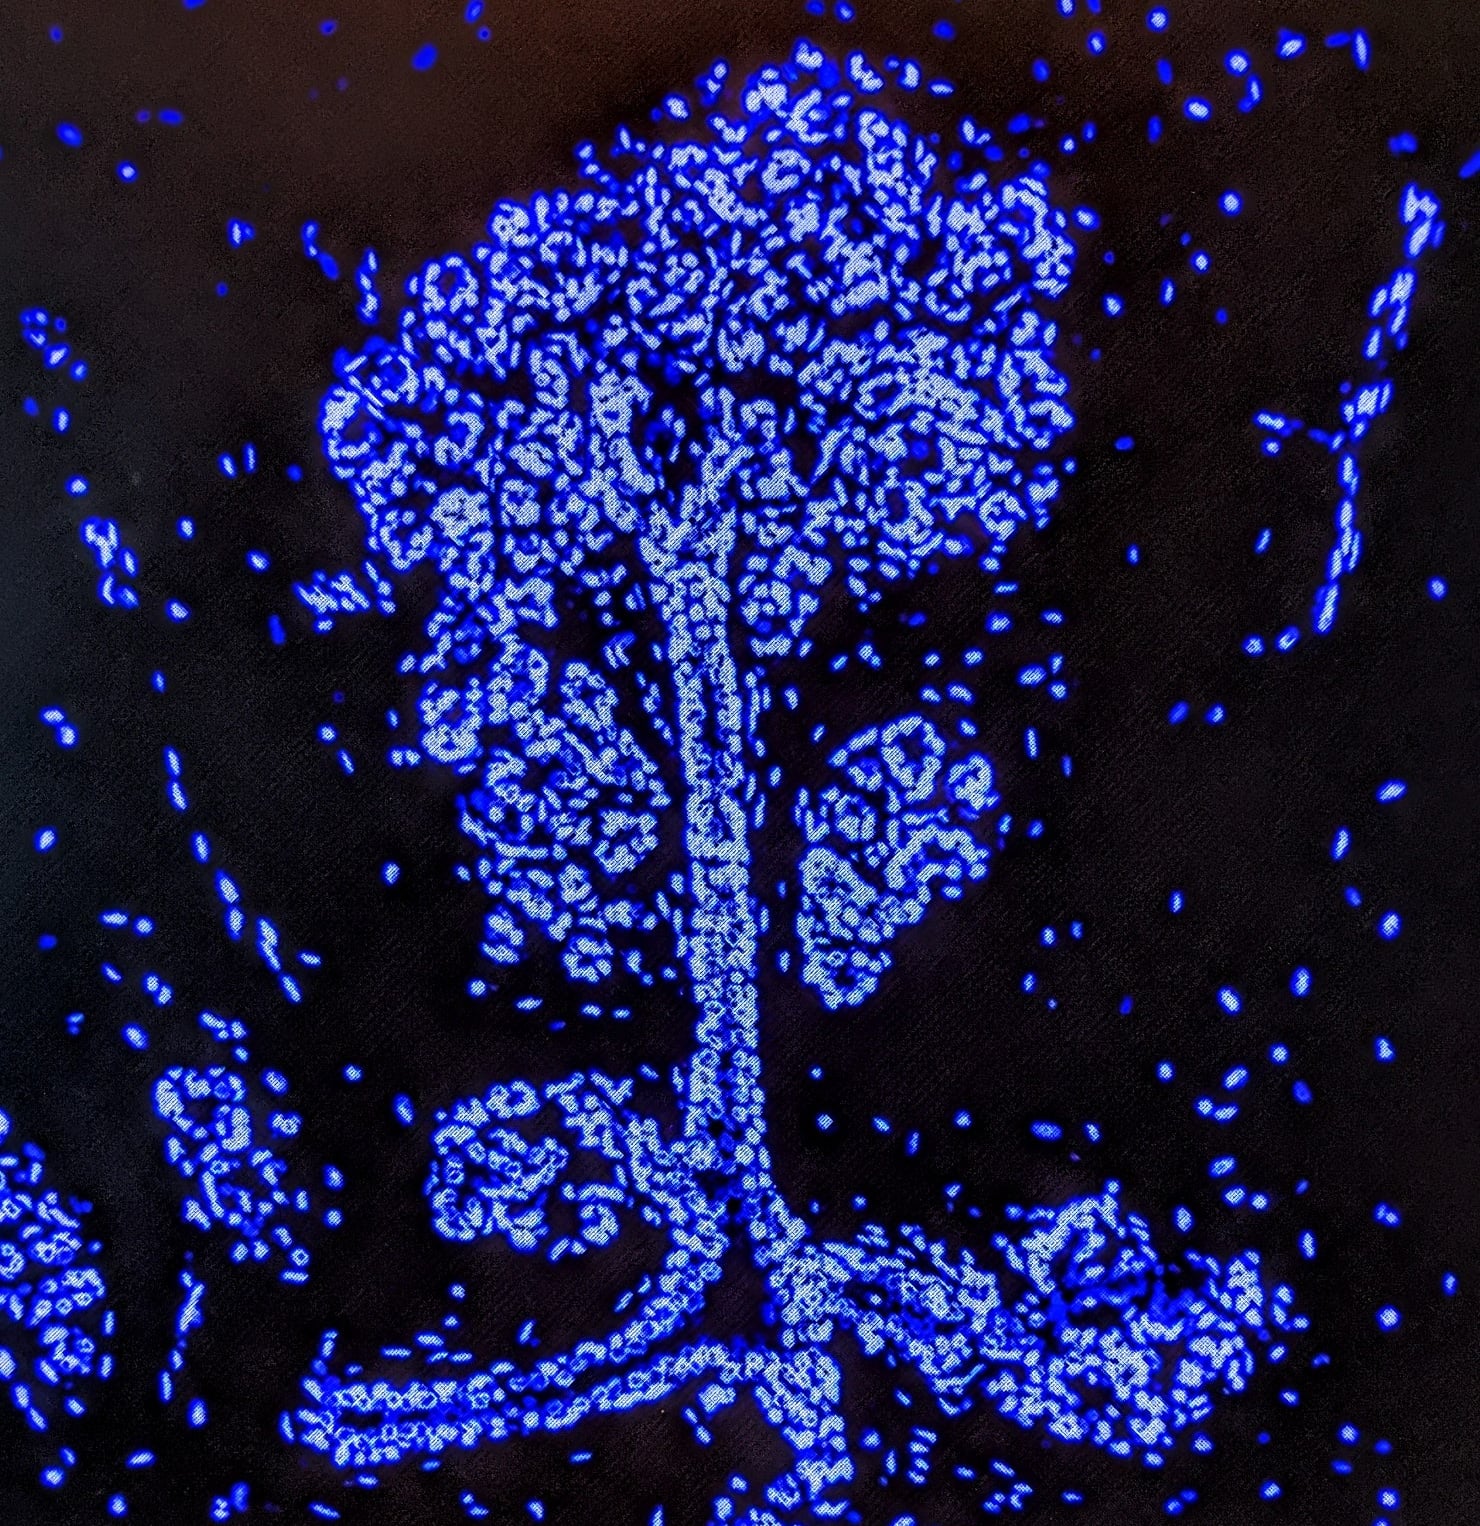

Priya Bhardwaj  Weill Cornell Medicine, New York, NY

This is a confocal microscopy image of human breast epithelium (blue color= Hoechst nuclear stain). Breast epithelium is comprised of tree-like branching ducts and lobules that respond to endocrine signals to synthesize and secrete milk during pregnancy and lactation. Breast epithelial cells can also become neoplastic in the setting of breast cancer, often times driven by hormones (e.g. estrogen, progesterone).